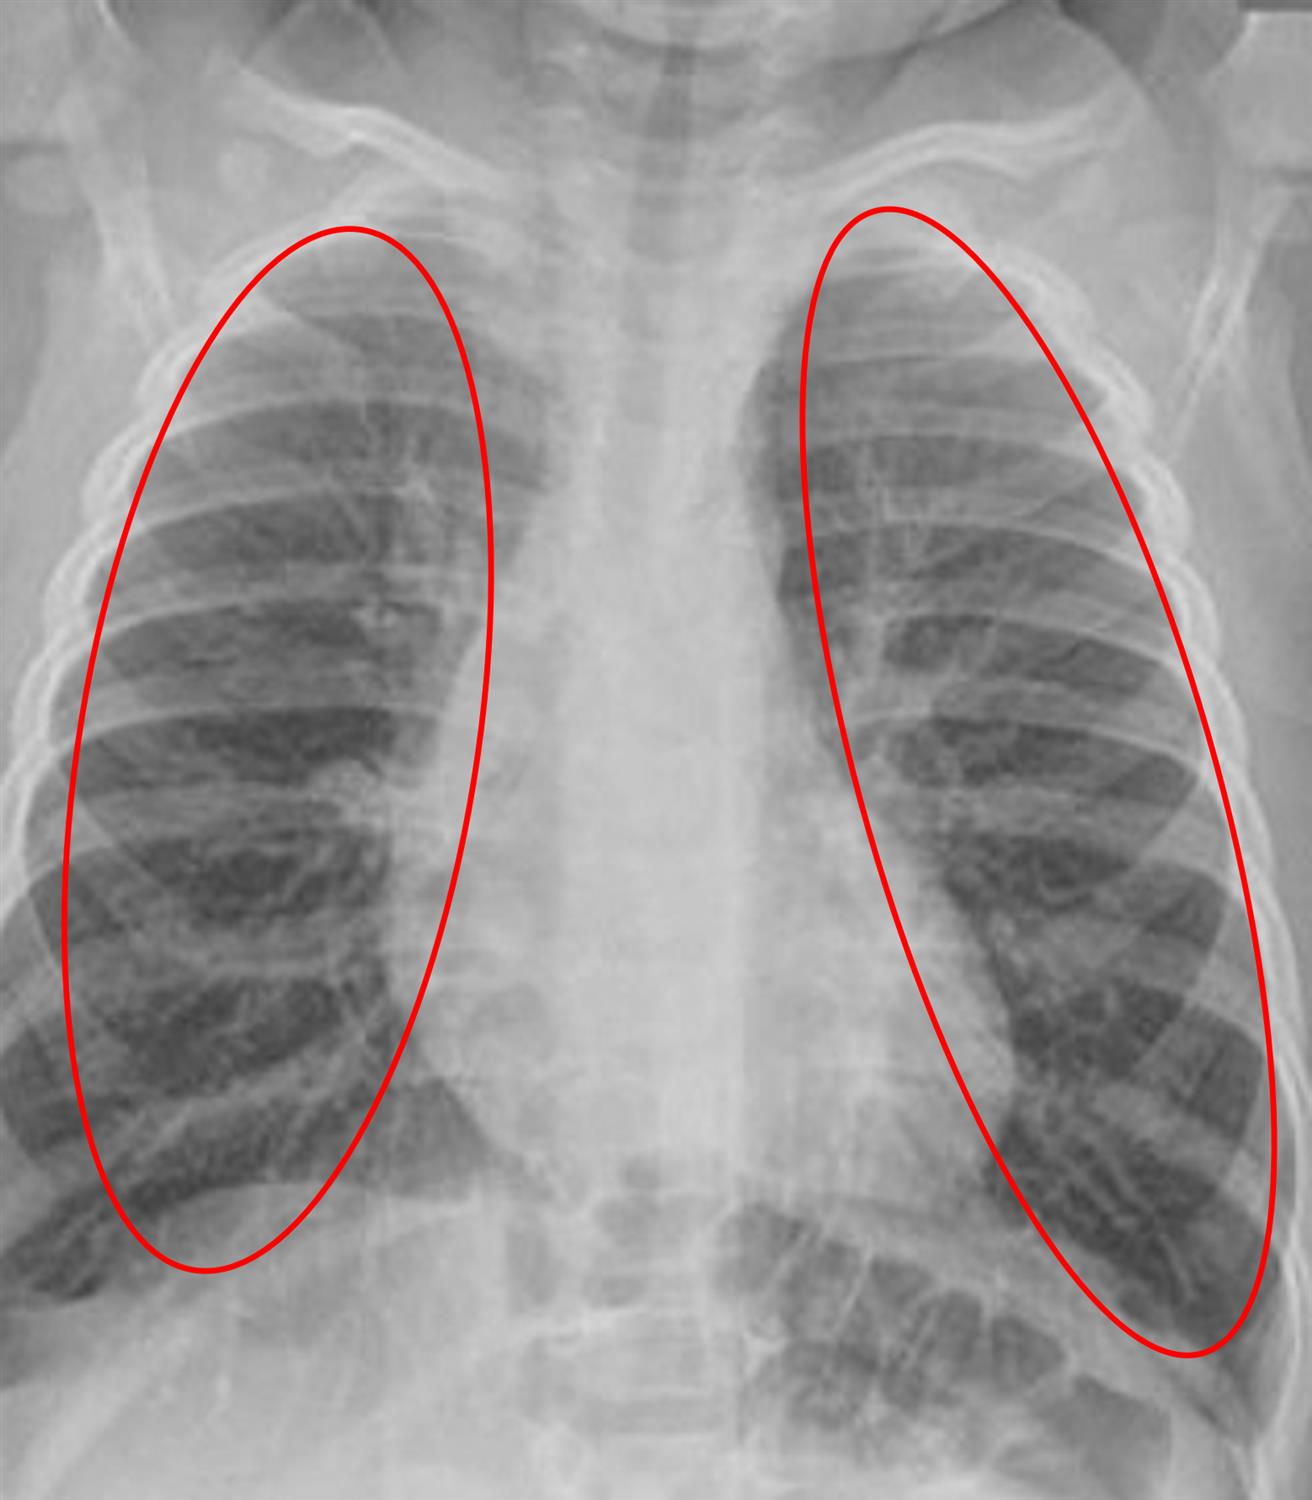

A 5-month-old boy is brought to the emergency department by his parents with a 2-day history of fever. His parents say that they initially treated him with acetaminophen at home; however, they became concerned when he started having difficulty breathing over the last few hours. During the past 3 months, the patient has had several upper respiratory tract infections and poor weight gain. The mother’s pregnancy and delivery were uncomplicated, and the infant’s immunizations are up-to-date. The patient is breastfed, but the mother notes he is eating less lately. His temperature is 101.4°F (38°C), blood pressure is 80/50 mmHg, pulse is 150/min, and respirations are 50/min. Pulse oximetry shows an oxygen saturation of 85% on room air. Physical exam reveals a child in respiratory distress. Crackles are heard diffusely in both lung fields. A chest radiograph is obtained, and the results are shown in Figure A. Laboratory results are notable for the following:

Figure/Illustration A is a chest radiograph demonstrating bilateral ground-glass opacities (red circles). These findings are consistent with pneumocystis jirovecci pneumonia.